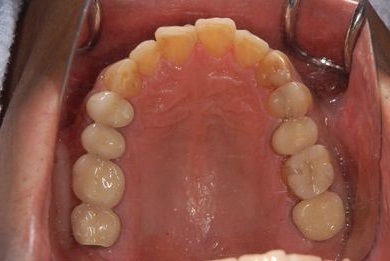

インプラント治療+セラミック治療+歯肉歯槽骨整形術

| 性別/年齢 | 男性 / 47歳 | ||||||||||||||||||||||||||||||||

| 主訴 | 悪いところの治療と、歯をきれいにしたい。 | ||||||||||||||||||||||||||||||||

| 治療方針 | 右下奥、保存不能な歯を抜歯し、インプラント治療にて、機能的・審美的回復を行う。 | ||||||||||||||||||||||||||||||||

| 治療内容 | インプラント2本、メタルボンドセラミッククラウン9本(メタルボンド用土台6本)、ハイブリッドセラミッククラウン2本(セラミック用土台2本)、ハイブリッドセラミックインレー5本、歯肉歯槽骨整形術 | ||||||||||||||||||||||||||||||||

| 治療期間 | 2年9ヶ月 |